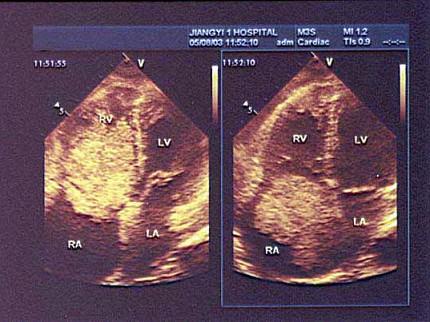

根据心尖四腔切面声像图所示,超声诊断为?(?)A.右房血栓B.三尖瓣赘生物C.右房黏液瘤D.正常声像图E.二尖瓣脱垂

问题 根据心尖四腔切面声像图所示,超声诊断为?(?)

选项 A.右房血栓 B.三尖瓣赘生物 C.右房黏液瘤 D.正常声像图 E.二尖瓣脱垂

答案 C